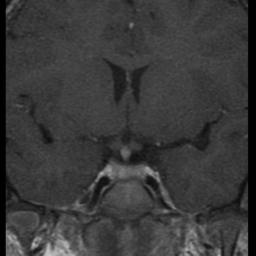

Niña de 7 años. Se solicita RM hipofisaria por pubertad precoz.

T1 + Gadolinio